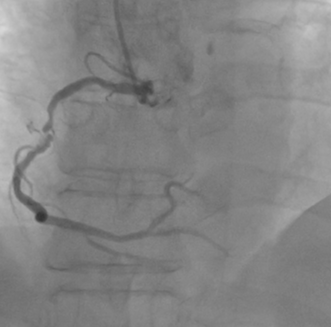

Right Coronary Angiography via right radial artery using 5 Fr TIG Optitorque demonstrated a tight lesion at mid part of Right Coronary Angiography (RCA) with heavy calcification. Left coronary angiography demonstrated non-significant stenosis at Left Anterior Descendent (LAD) and Left Circumflex (LCx) arteries. Therefore, the patient was planned to undergo PCI procedure via femoral access with IVUS guidance and preparation for rotablation.

PCI began by engaging a 7Fr JR 4.0 to the RCA ostium via right femoral artery. Wiring initially performed with Runthrough NS through Fine Cross microcatheter, but wire entered subintimal space. Several manipulations to reposition the wire were unsuccessful. Immediate contrast injection showed no flow to the distal part due to abrupt closure of the RCA Patient became angina with marked ST-segment elevation. Rewiring was immediately attempted using Fielder XT-A through Fine Cross microcatheter and the wire successfully entered true lumen A 1.5 x 1.5 mm NC balloon was placed at the lesion but balloon ruptured.A 2.0 x 15 mm NC balloon with extension catheter as support but balloon ruptured.Finally A 2.0 x 20 mm NC scoring balloon successfully inflated then flow was restored with TIMI III flow.Angina relieved, ST-segment lower and hemodynamic improvedIVUS showed massive-compressive intra mural hematoma along distal to proximal RCA with intimal tear of dissection, and the wire within false lumen at mid part RCA.Coronary fenestration attempted using 3.0 x 15 mm NC scoring balloon inflation with dual guidewire inside the lumen.Hematoma surprisingly propagated marked by contrast trapping and no flow to PLBFenestration performed again using 2.5 x 15 mm NC scoring balloon and flow successfully restored.Four DES finally decided to be deployed at distal to ostial RCAFinal angiogram showed excellent result with TIMI III flow, hematoma was disappeared with good stent apposition on IVUS examination